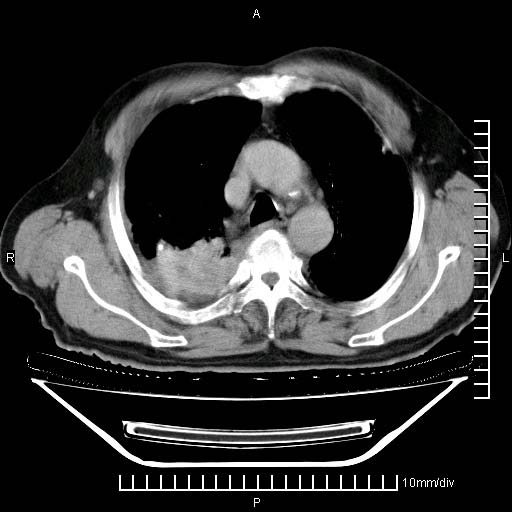

标题: CT24043:胸部增强:男性,60岁

既往肺结核,近10几天,咳嗽,咳痰,右侧胸痛,疼痛较明显,右上肺斑块考虑结核灶胸膜粘连,增强,可惜动脉期没有定好,未见强化,可延迟4分后又见较明显强化,中心见低密度影,如果说结核是边缘强化,可这个灶强化的面积挺大的,让人很挠头。

动脉期